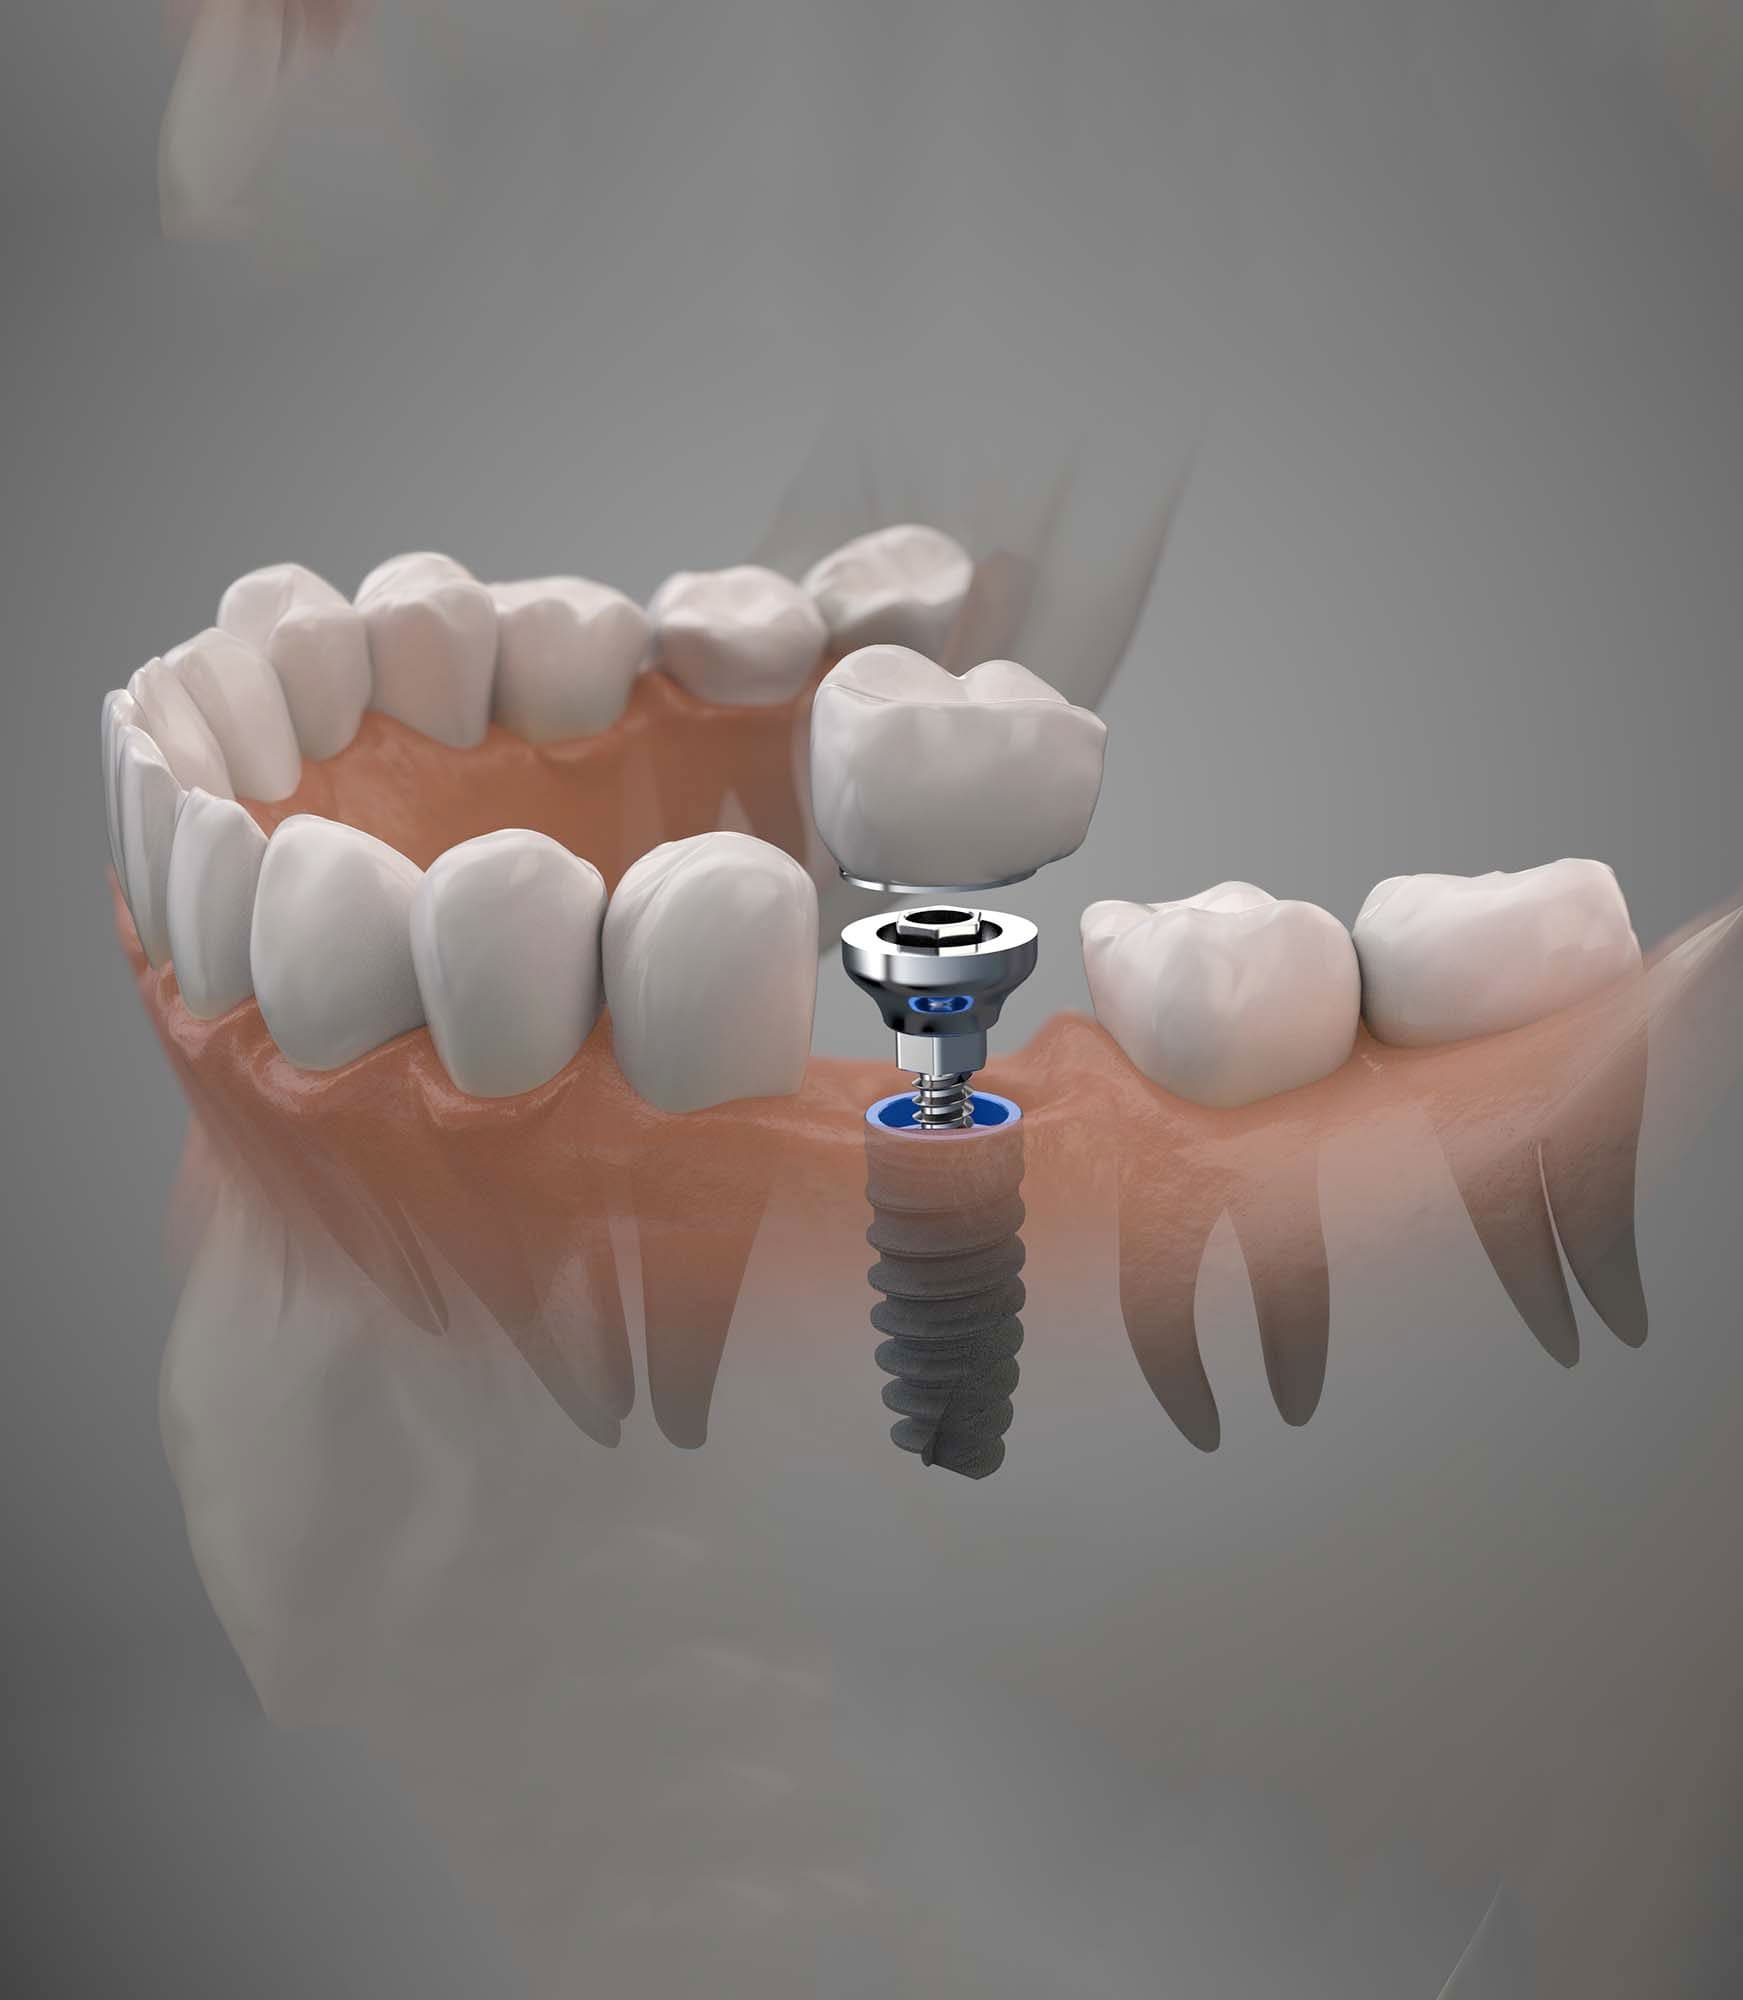

Современные коронки на зубные импланты: виды и фото-примеры